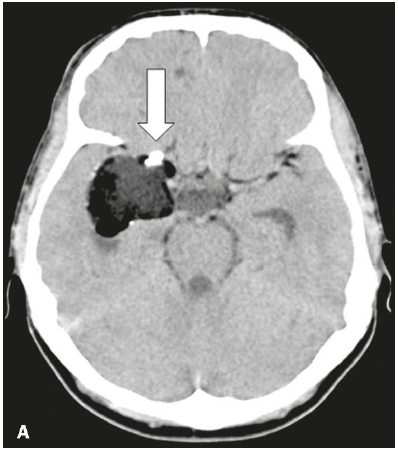

Observe a tomografia, abaixo:

Fonte: https://www.scielo.br/scielo.php?pid=S0100-39842020000400273&script=sci_arttext&tlng=pt

O processo expansivo, demonstrado à imagem, é característico de: